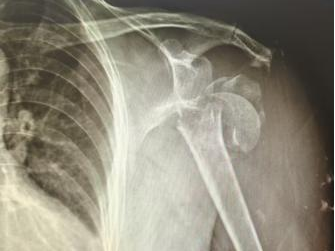

患者是71岁的女性,因在家中不慎跌倒,导致右肱骨近端粉碎性骨折伴肱骨头脱位,右肩功能完全丧失。传统内固定手术因患者骨质疏松严重,存在较高失败风险。面对这一挑战,创伤二科占卫兵主任团队迎难而上,经过充分术前评估,符合半肩关节置换术的手术指征,决定采用半肩关节置换这一先进术式。

▲患者术前